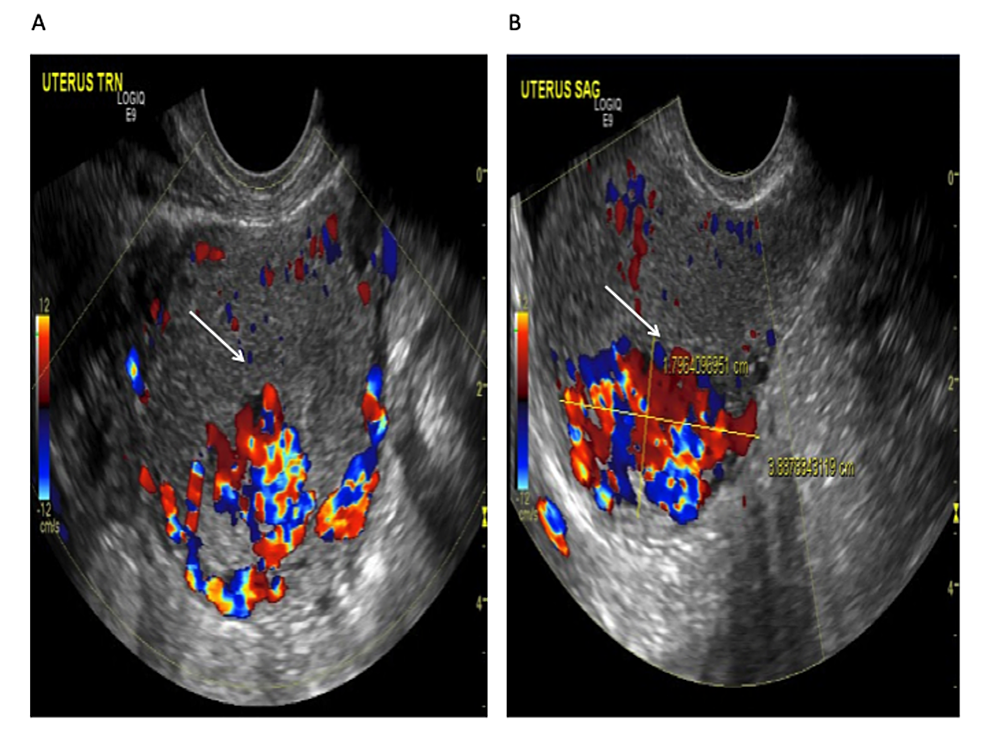

Transvaginal ultrasound revealed a 3.9 cm x 2.7 cm x. 1.8 cm sized anechogenic cystic space in the posterior wall of the fundus as seen in Figure 1, and with Doppler application, demonstrated marked vascularity (Figure 2). For further evaluation, pelvic magnetic resonance imaging (MRI) was performed, which revealed a contrast-opacified structure within the wall of the myometrium. Focal serpiginous flow voids were also noted within the posterosuperior myometrium with extension to the myometrial canal (Figure 3).